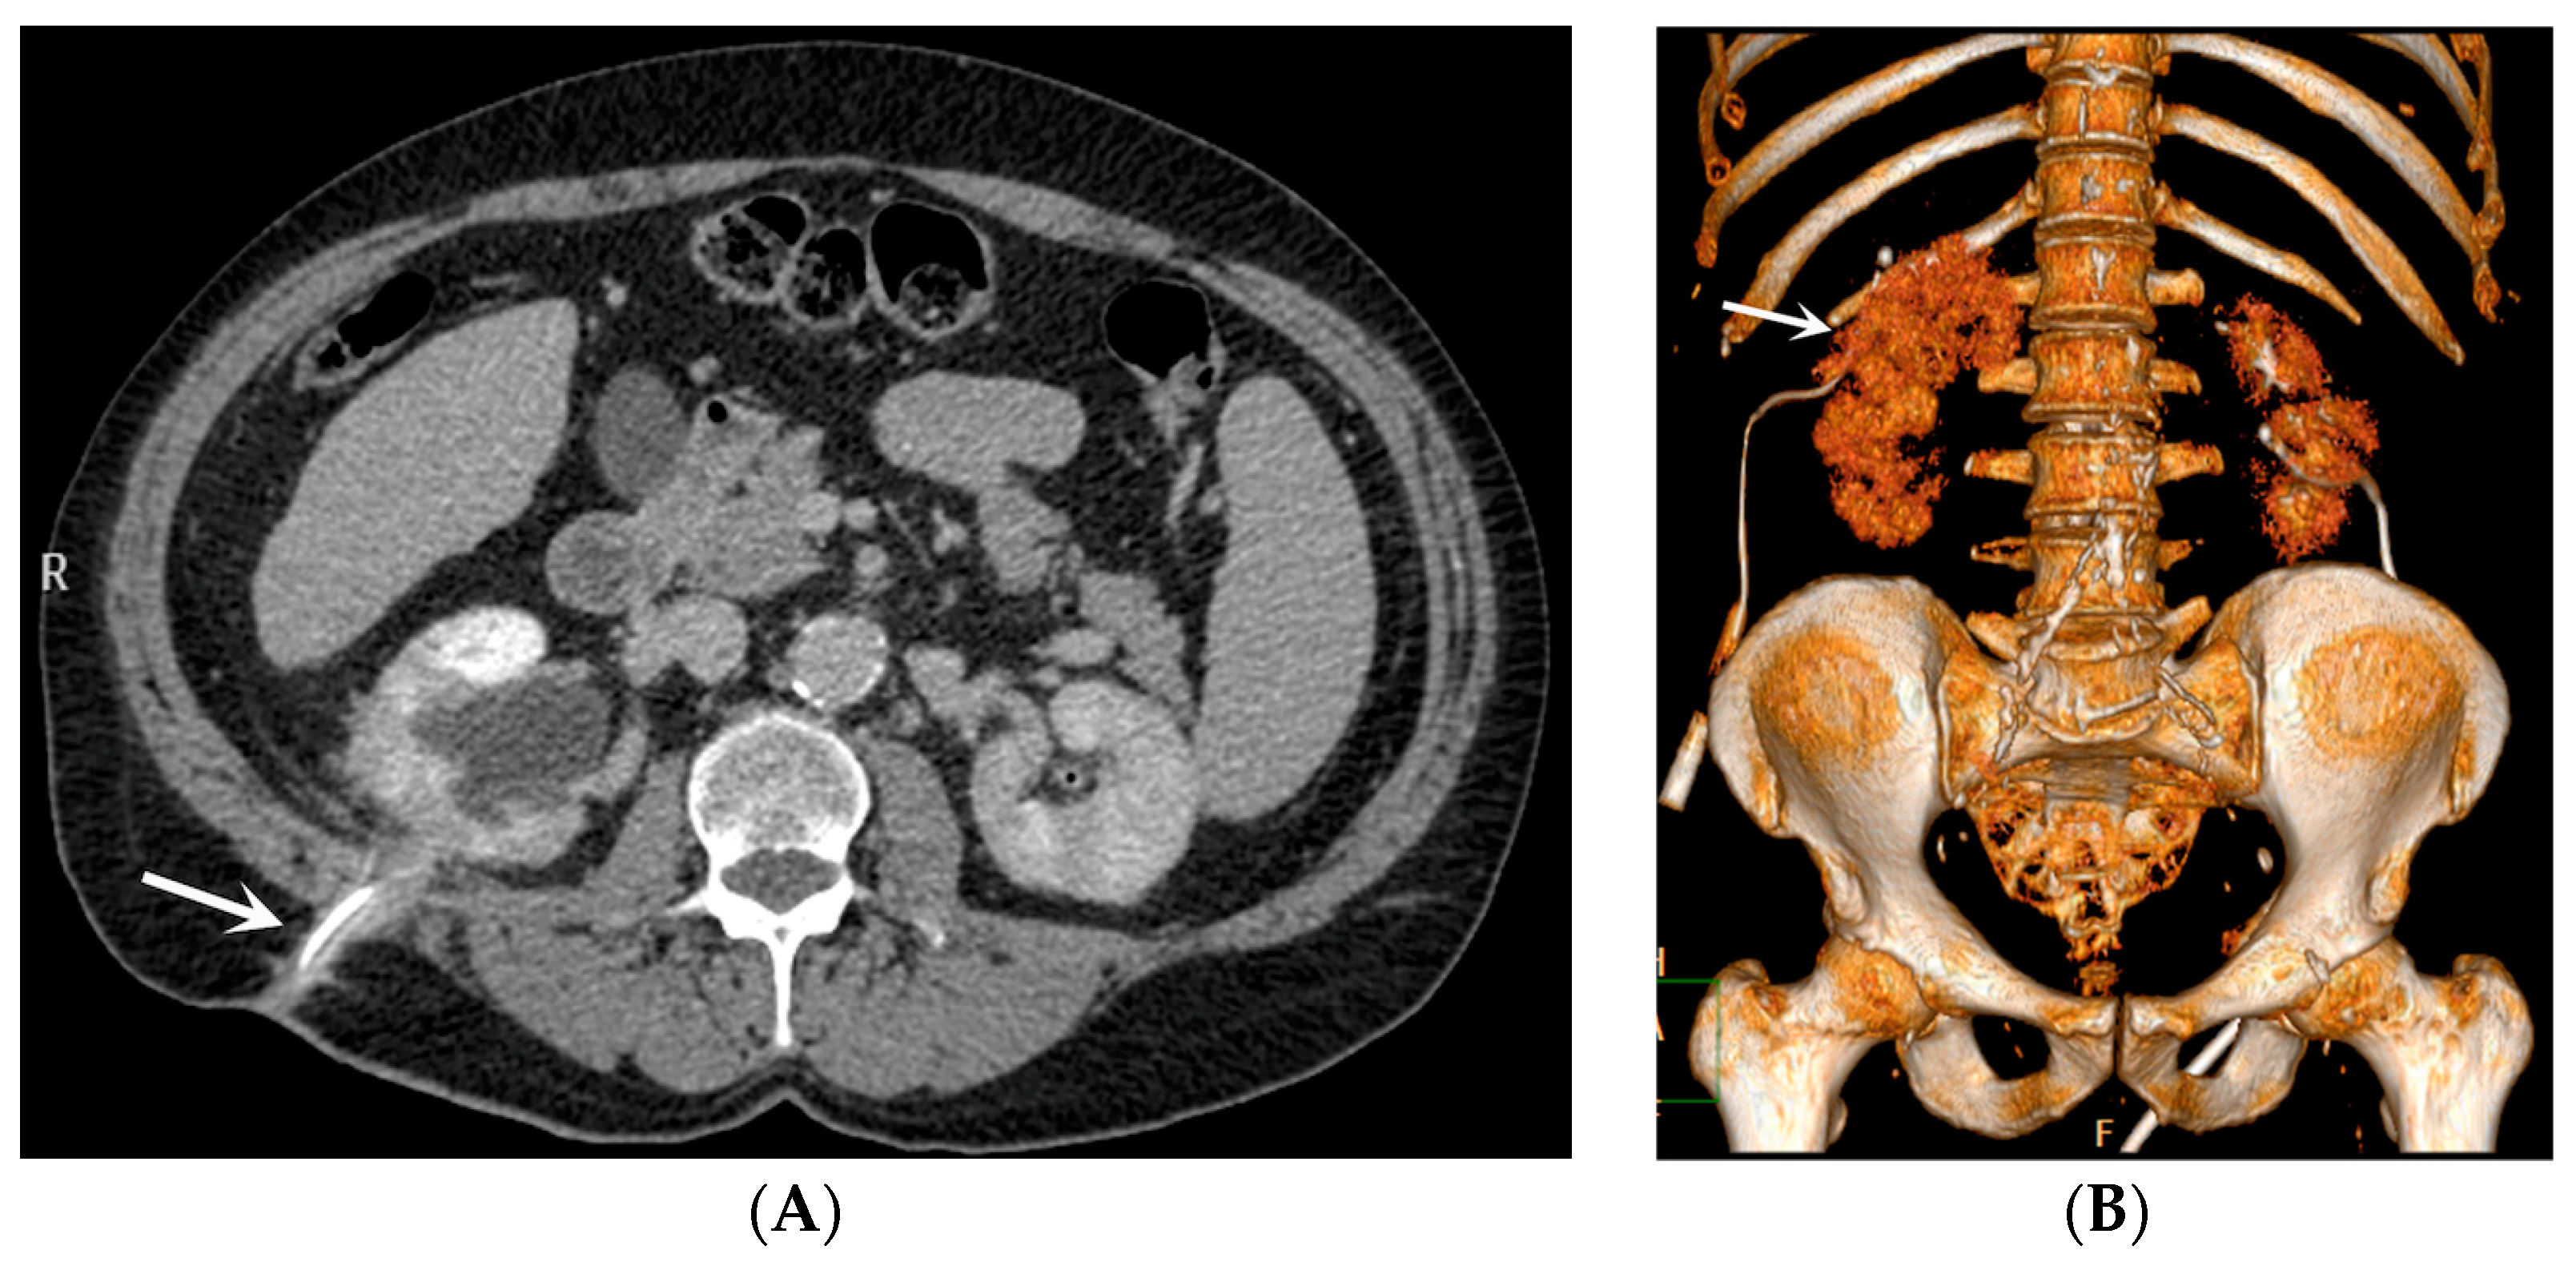

- Bleeding: The erosion of the stent into the arterial system is a rare and feared complication of ureteral stent placement, which can cause hematomas (Figure 10 and Figure 11), active bleeding, or pseudoaneurysm (Figure 12, Figure 13 and Figure 14). To avoid mortality from these complications, a high level of clinical suspicion is essential. Intermittent hematuria in a patient with a stent is typically the usual clinical scenario. However, massive hematuria and circulatory collapse can occur due to the manipulation of the ureteral stent [2,39].